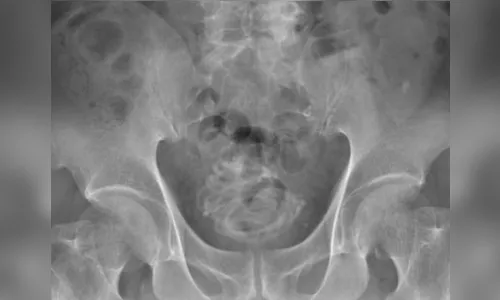

Um homem de 79 anos surpreendeu médicos após chegar ao hospital reclamando de dores ao urinar. Depois de realizar exames de imagem para verificar a origem do desconforto, a equipe médica se assustou ao ver que o paciente tinha uma corda de pular de 2,3 metros na bexiga.

“Primeiro realizamos um ultrassom e identificamos um objeto grande na bexiga do paciente. Depois fizemos um raio-x, que revelou um corpo estranho enrolado em forma de fio. Em seguida, fizemos uma tomografia que nos ajudou a escolher o melhor jeito de tirar a corda e usamos um programa de computador em 3D para nos direcionar. Percebemos que seria impossível puxar a corda pelo pênis”, disse Toshiki Kijima, professor de urologia na Dokkyo Medical University, autor do relatório publicado no periódico.